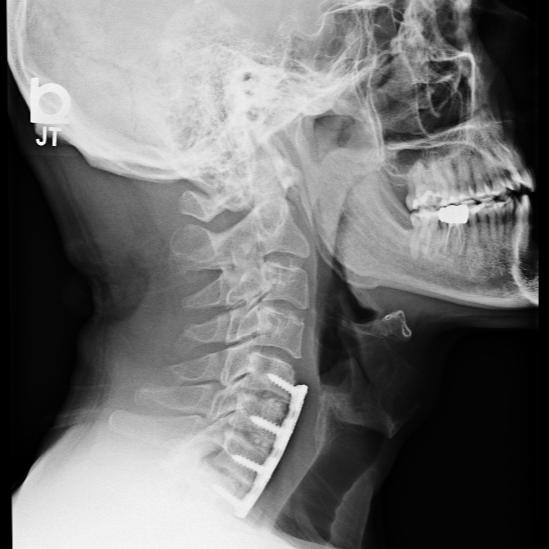

"As you might imagine, I had x-rays and an MRI done. After these were evaluated, I found myself in an office talking to Dr. Hunt, who told me I needed neck surgery. I never expected this and was a little freaked out--not solely because of how much functioning I had lost, but also because the prospect of surgery was pretty nerve-wracking. I spoke to Theresa, who got me scheduled very promptly, and in about two weeks I had ACDF surgery (with three fusions)."

"So my surgery was on 23 Feb 2021 - as I type this it is just over six months later (mid Sept). As far as how I am now, I went from walking with a limp (right leg was very impaired), having weird 'electric shocks' throughout my body, being physically numb over a good bit of my body, and having nearly no hand strength - and now, almost 100% back to normal after six months. I was unable to drive, play the drums, and go to the gym. I actually had trouble standing before surgery!"

"The first time I put my feet on the floor in post-op after my operation, I could tell my hips were more stable. I didn't feel like I would fall. I wasn't swaying like I had that very morning. I was able to walk to the bathroom unassisted. When I got home after surgery, the only thing I was allowed to do initially was walk. So I did every day, and added things to my routine as I could."